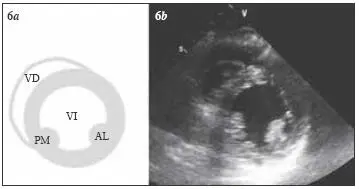

Fig 36 Visión del plano paraesternal de eje corto transversal a nivel de - фото 32

Fig. 3.6 Visión del plano paraesternal de eje corto (transversal) a nivel de los músculos papilares (medio). AL = músculo papilar anterolateral; VD = ventrículo derecho; VI = ventrículo izquierdo; PM = músculo papilar posteromedial.